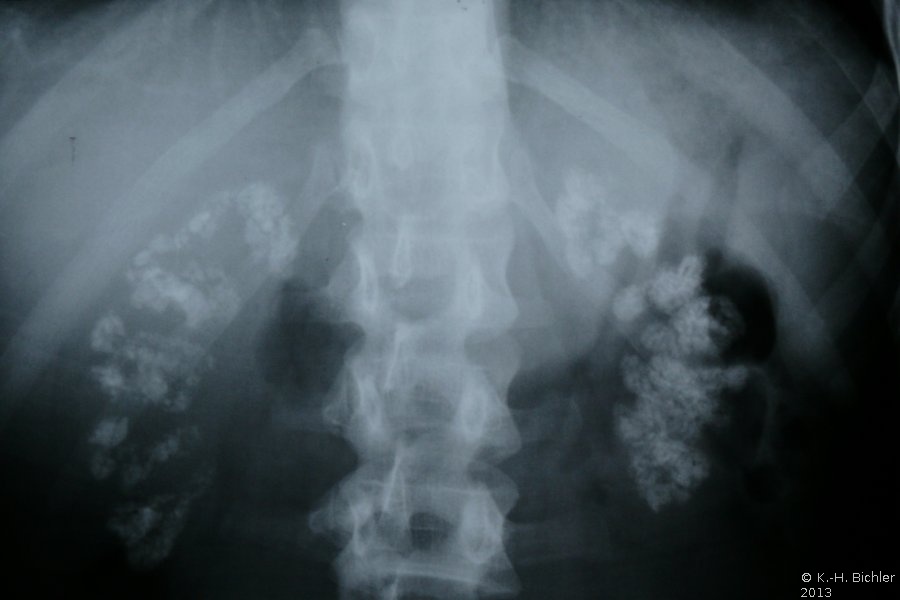

Die Diagnose wird ausgehend von der Sonographie gestellt (Abbildung 2). Zur Kontrolle der Abflussverhältnisse aus dem oberen Harntrakt ist ein i.v.-Pyelogramm empfehlenswert. Die typischen radiologischen Veränderungen im Pyramidenbereich der Markschwammniere werden im AUR erfasst (Abbildung 1). Das Röntgenbild zeigt die Kolbenförmigen, z.T. verplumpten Auftreibungen der Sammelrohre mit multipler Steinbildung.

Beispiele: Röntgenbilder (Abbildung 3).